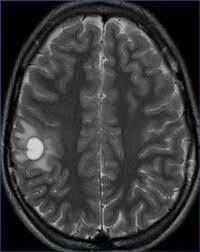

Se pueden apreciar _______ en T2 y FLAIR.

• Hiperintensidades calloseptales

¿Qué hallazgos en RM se pueden encontrar en la esclerosis múltiple,?

• Pequeñas (5 a 10 mm), lineales y ovoides

• Dedos de Dawson

• Periventriculares